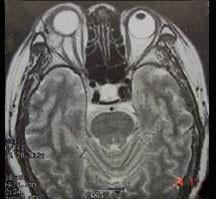

问题 男性,41岁,右侧眶外上方肿胀,可触及无痛性包块,CT及MRI检查如图所示,请选择最可能诊断()

选项 A.眶内血管瘤 B.眶内结核 C.眶内炎性假瘤 D.泪腺混合瘤 E.眶内囊肿

答案 D